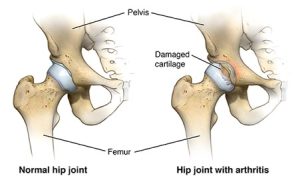

عکس شماره ۱: تعویض مفصل ران

آرتروز (استئوآرتریت): این بیماری تخریبی مفصل، معمولاً با افزایش سن بروز میکند و باعث تخریب غضروف مفصل ران میشود که منجر به درد و محدودیت حرکتی میگردد.

عکس شماره ۲: آرتروز مفصل ران